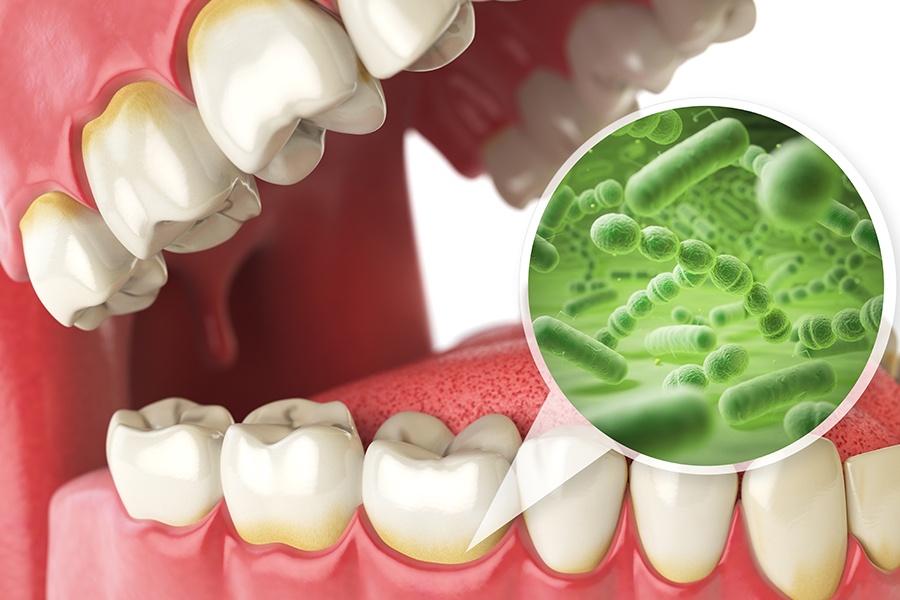

虫歯はお口の中の細菌による感染症ですが、日常的な習慣や癖など様々な要因が影響しているケースも多くあります。そのため、毎日しっかり歯磨きをしているつもりでも、虫歯を繰り返してしまうという方は、虫歯リスクを高める原因が他にある可能性があります。

虫歯リスクを高める要因としては、以下のような項目に注意が必要です。

口呼吸をしている場合など、口の中が乾燥した状態が長く続くほど細菌が増殖しやすくなるため虫歯リスクが高まります。

歯の表面の溝が細菌の塊(プラーク)の入り込みやすい形状の場合など、虫歯リスクは高くなります。

子どもの虫歯の原因としては、周囲の大人の唾液などを介して虫歯菌に感染してしまうことや、お菓子やジュースなど甘いものを時間をかけて口にすることなどが挙げられます。また、乳歯は大人の歯と比べて歯質が弱く、虫歯の原因となる菌への抵抗力も低いため、より虫歯になりやすい状態と言えます。